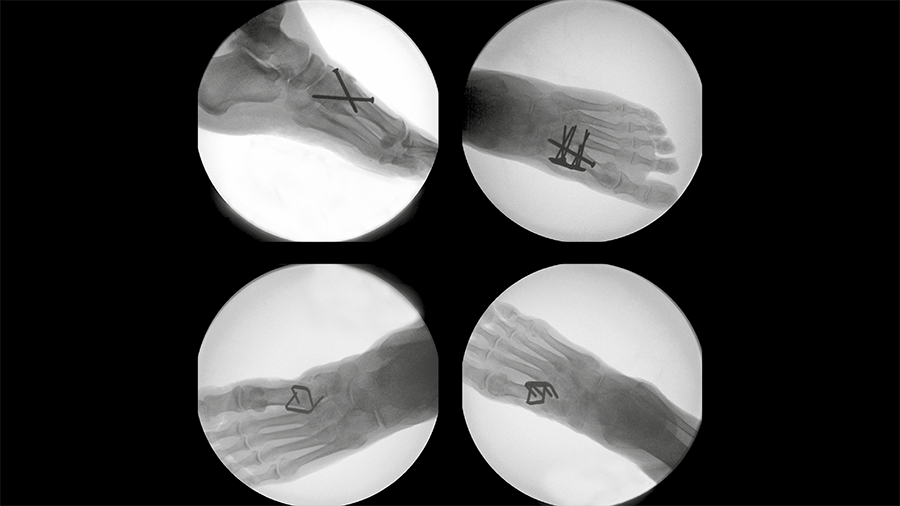

Ten pairs of fresh-frozen human anatomical tibiae with a simulated AO/OTA 42-A3.1 fracture were assigned to two groups for reamed intramedullary nailing using either a nonangular stable ETN with three distal screws or the novel TN-A with two distal angular stable low-profile retaining locking screws (Fig 2). Testing conditions included quasi-static and progressively increasing combined cyclic axial and torsional loading in internal rotation until failure of the bone-implant construct, with monitoring by means of motion tracking (Fig 3).

Nitinol stables might demonstrate comparable performance to established techniques for fusion of the first TMT joint.